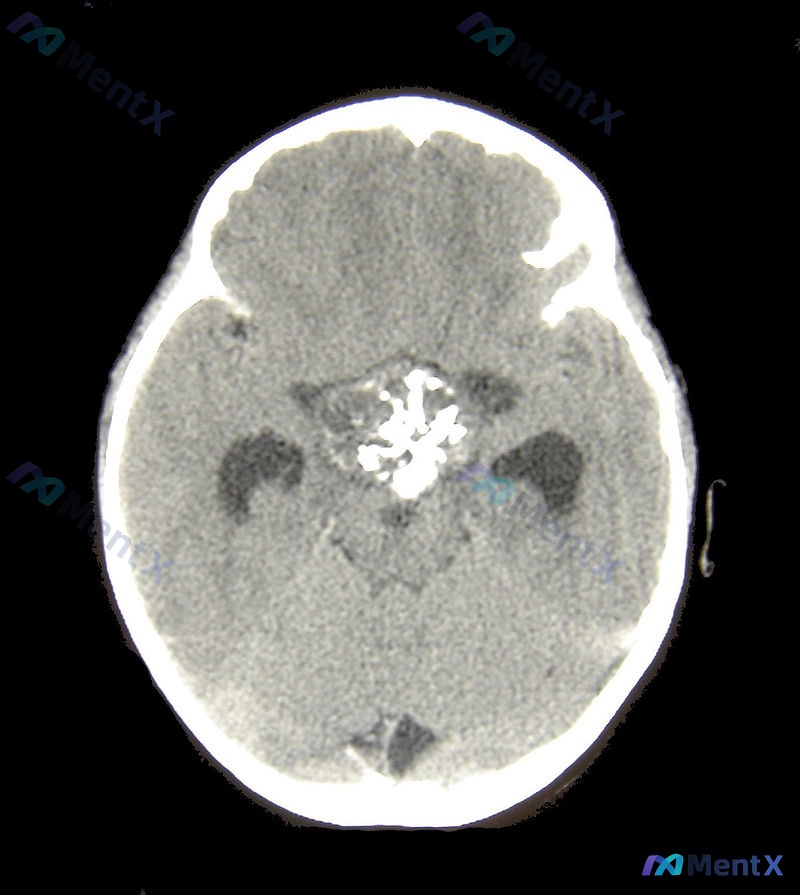

整理了一个儿科病例,很考验临床思维,放出来大家一起讨论一下: 11岁男孩,近一周反复呕吐,晨起症状更重,白天会有所缓解,偶尔头痛,几天前有过腹泻。患者饮食正常,兄弟近期也有腹泻,都已经自行痊愈。 生命体征:体温37.5°C,血压80/45mmHg,脉搏90次/分,呼吸16次/分,氧饱和度98%。 体...